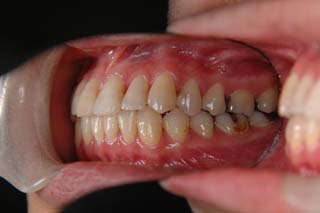

(叢生/正中変位/上右小臼歯抜歯(片顎片側抜歯)/ ハーフリンガル)

骨格的な非対称や治療前に見られた咬耗など、対処が難しい問題もありますが、前歯部被蓋、臼歯関係ともに良好です。今後、保定管理を継続する予定です。